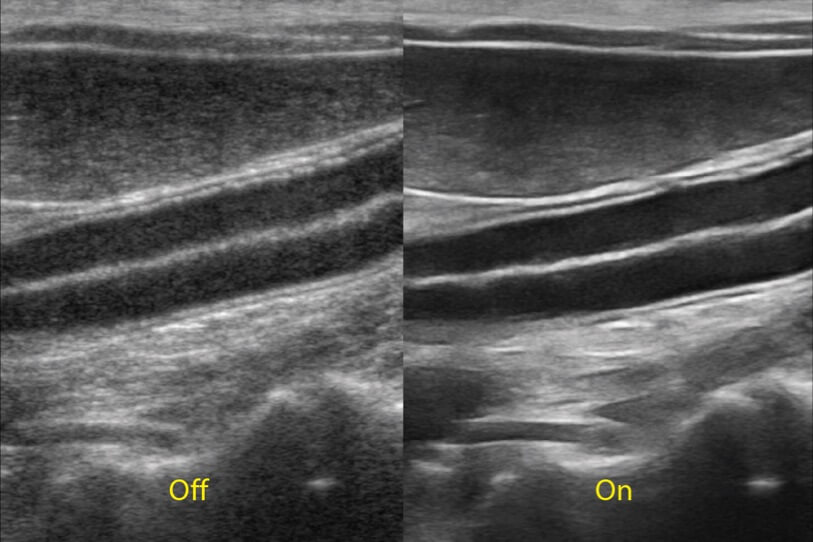

ProPet 70 進(jìn)一步提升了微米成像算法,更加注重對基礎(chǔ)原始圖像的還原和保留,在有效減少斑點(diǎn)噪聲、增強(qiáng)組織邊界顯示的同時,避免過度優(yōu)化丟失真實(shí)的解剖信息。